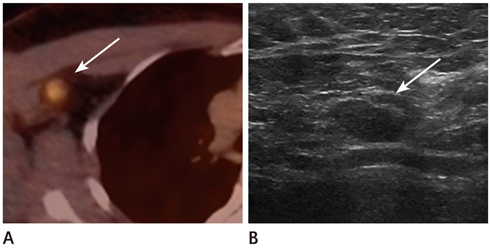

Our database revealed 922 breast cancer patients who underwent surgery from January 2008 to July 2011. We included 20 patients with negative findings on routine follow-up but with new hypermetabolic lesions on FDG-PET/CT. All underwent second-look examination [breast ultrasound (US) = 14, chest CT scan = 6]. A total of 17 cases were pathologically verified and 3 were diagnosed with follow-up imaging.

The locations were in the axillae (n = 7), breast (n = 6), chest wall (n = 3), cervical/supraclavicular (n = 3), and internal mammary (n = 1). Of the 20 hypermetabolic lesions, 10 were pathologically confirmed malignancies. Of the 14 patients who had undergone US, 7 had suspicious findings and 5 were confirmed as malignancies. Of a total of 6 patients who had undergone CT scans, 5 had suspicious findings and all turned out to be malignancies. The positive predictive value of the second-look examination was 83.3% (10/12).

Second-look examination and pathologic confirmation should be performed for newly appearing hypermetabolic lesions on FDG-PET/CT in order to exclude loco-regional recurrence in breast cancer patients.